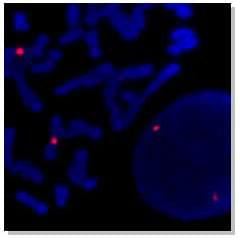

Próbki sond FISH:

Sygnał hybrydyzacji ludzkiej sondy genowej XIST ( czerwony) |